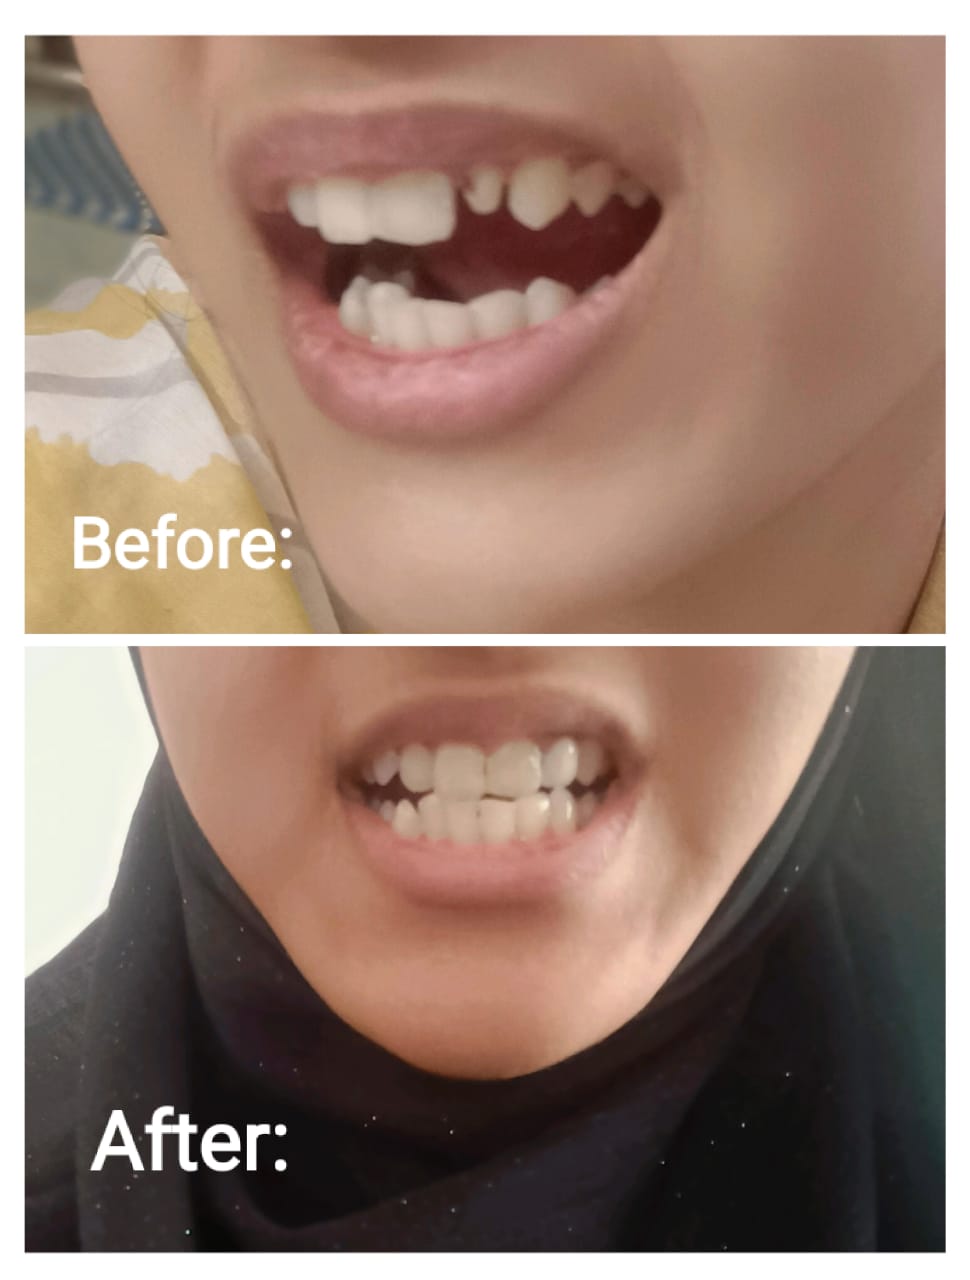

Categorized images from our clinic and outreach activities.

Special activity photos from January 30, 2026.